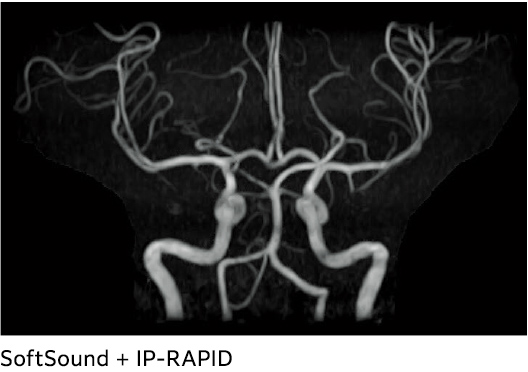

AutoClip*1

Baş MRA görüntülerinin otomatik olarak kırpılan görüntülerini oluşturan dijital görüntü işleme işlevi.